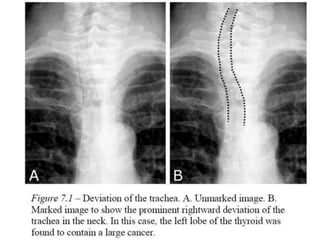

Trachea

• Upper part- midline

• Lower part- deviates slightly around aortic

knuckle- marked on expiration

• Left bronchus not clearly visualized due to

aorta

• 25mm in males , 21 mm in females

• Right paratracheal stripe- 60% N- 5mm

• Angle of carina- 60 -75 degrees